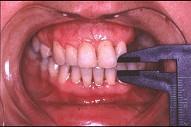

问题 关于颞下颌关节强直(如图)的描述哪项是正确的 ( )

选项 A.颞下颌关节外强直是关节外纤维黏连 B.颞下颌关节内强直是关节内骨性黏连 C.混合性下关节强直是指关节内,外强直同时发生,又称颌间挛缩 D.关节及关节周围组织器质性病变造成开口困难或完全不能开口 E.颞下颌关节强直常常突然发生